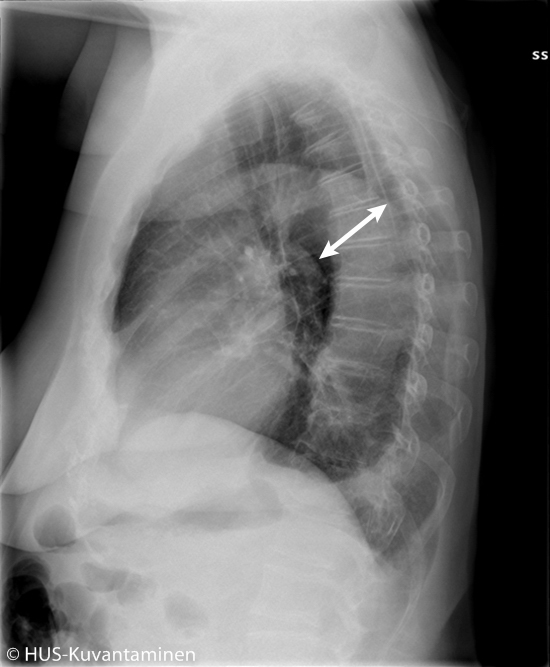

Aortan dissekoituma keuhkokuvassa (sivukuva löydösmerkinnöin).

Sivukuvassa on nähtävissä normaalia leveämpi laskeva aortta. Potilaalla oli B-tyypin aortan dissekoituma. Vasemmalla hieman pleuranestettä.